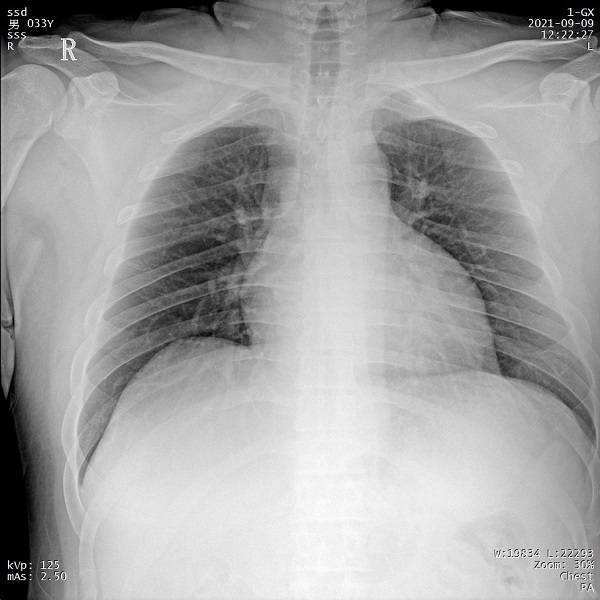

一、肥胖患者、組織較厚部位清晰成像

管電流大小與設(shè)備輸出X射線的能力相關(guān),管電流越大,設(shè)備輸出的射線量越充沛。PLX5500的管電流達(dá)到了710mA,輸出的射線能夠滿足各體型患者的拍攝需求,即便是體重達(dá)上百公斤的患者,也能夠獲得清晰的圖像。